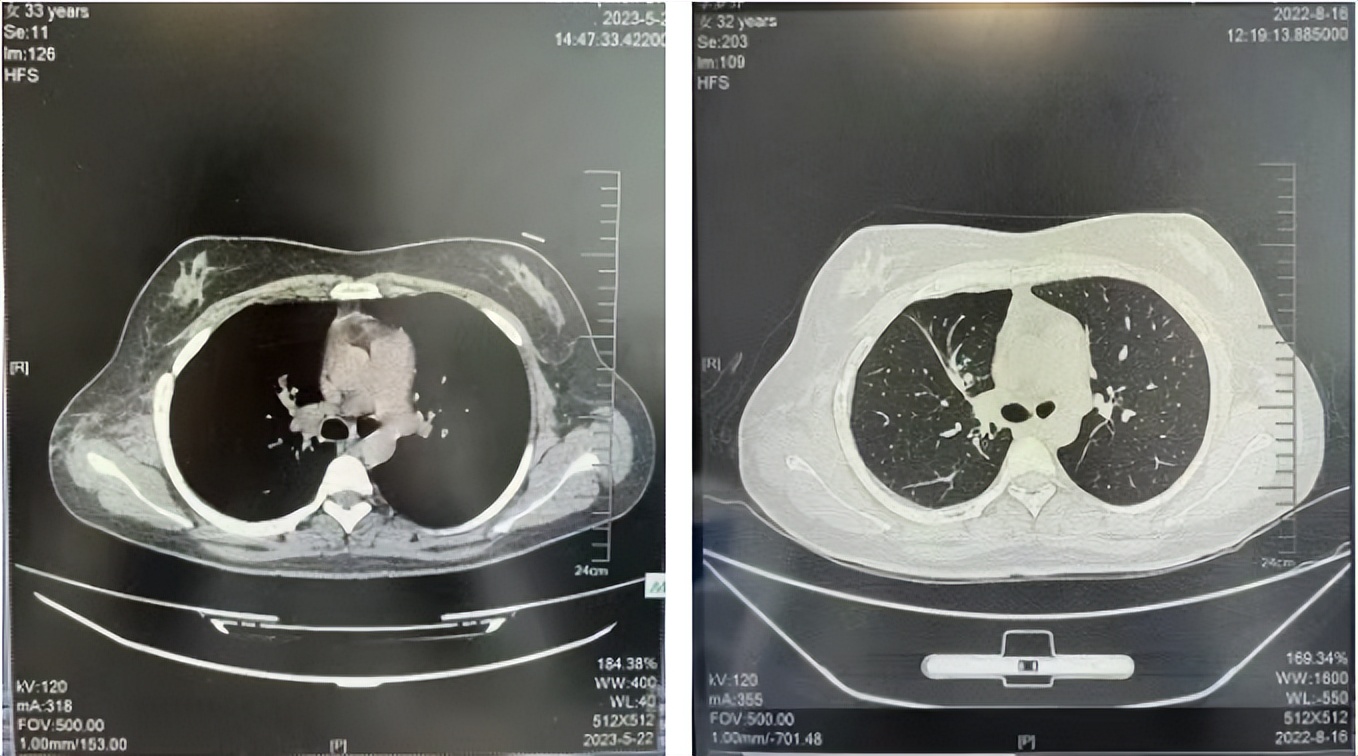

2016年1月复查CT提示支气管截断可见新发小结节,一线治疗采用培美曲塞+DDP方案化疗4周期(培美曲塞3.36,DDP 480mg)。化疗后复查胸部CT:右肺见不规则结节样影,最大层面大小约19mm*8mm,较前比较明显增大,疗效评估PD。2017.3-2017.4予单药多西他赛化疗3周期,疗效评估SD。2018年5月末复查CT提示结节较前增大,评效为PD,2018年6-10月予多西他赛+CBP化疗4周期,疗效评估SD。2022年5月患者出现活动后气短,复查胸部CT示右肺膨胀不良;右侧胸腔积液增多。胸腔积液包埋病理示符合肺腺癌细胞。行NGS基因检测:EML4:exon13-ALK:exon20融合。PD-L1(克隆号22C3)TPS<1%。

2018.07

2022.05

2022.08

2023.05

2024.12